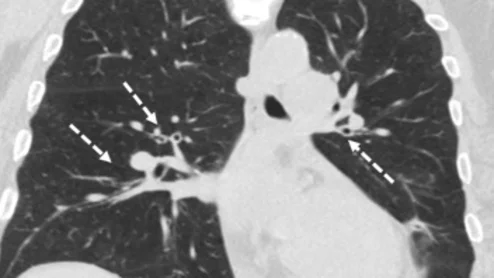

Marijuana may cause less lung damage than cigarettes

Many have touted smoking marijuana as a safer alternative to cigarettes. New imaging data offer clarity on whether this notion is actually true.